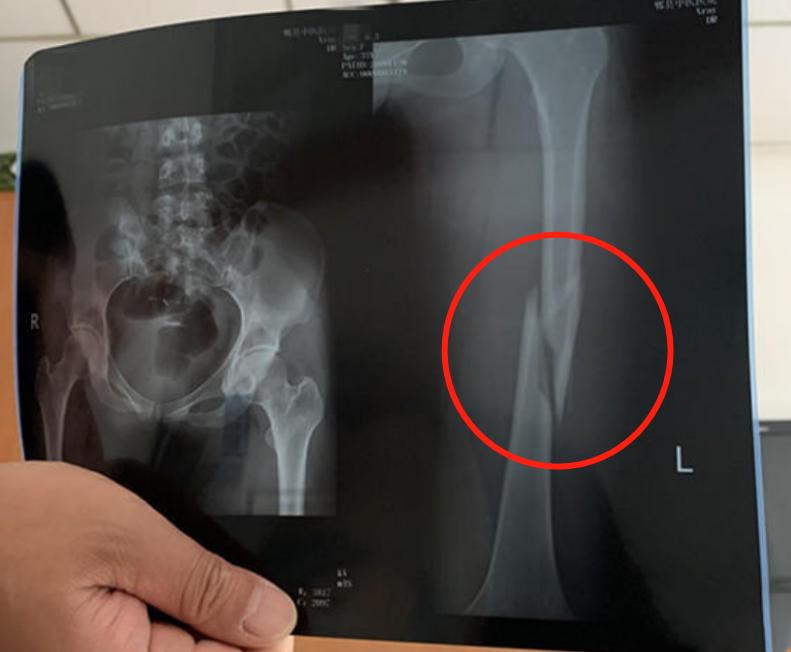

练瑜伽股骨骨折

李女士是成都人,她在郫都区的菩树瑜伽练瑜伽已经有一年多的时间了。前几天,她像往常一样来这里锻炼,教练辅助拉伸的时候,她感到大腿一阵剧痛,随后就被送往医院,医生诊断为股骨骨折。